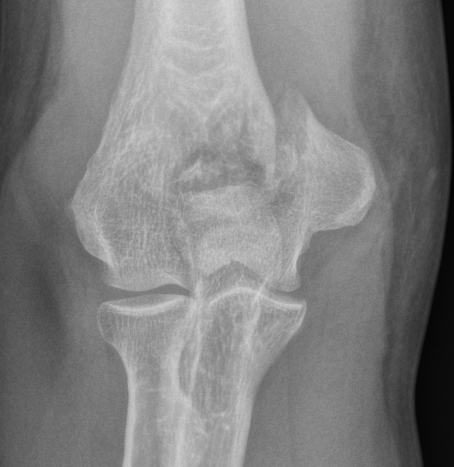

OTA / AO Classification

Type A: Extra-articular fracture

Type B: Partial articular fractures

Lateral condyle Medial condyle

Type C: Complete articular fractures